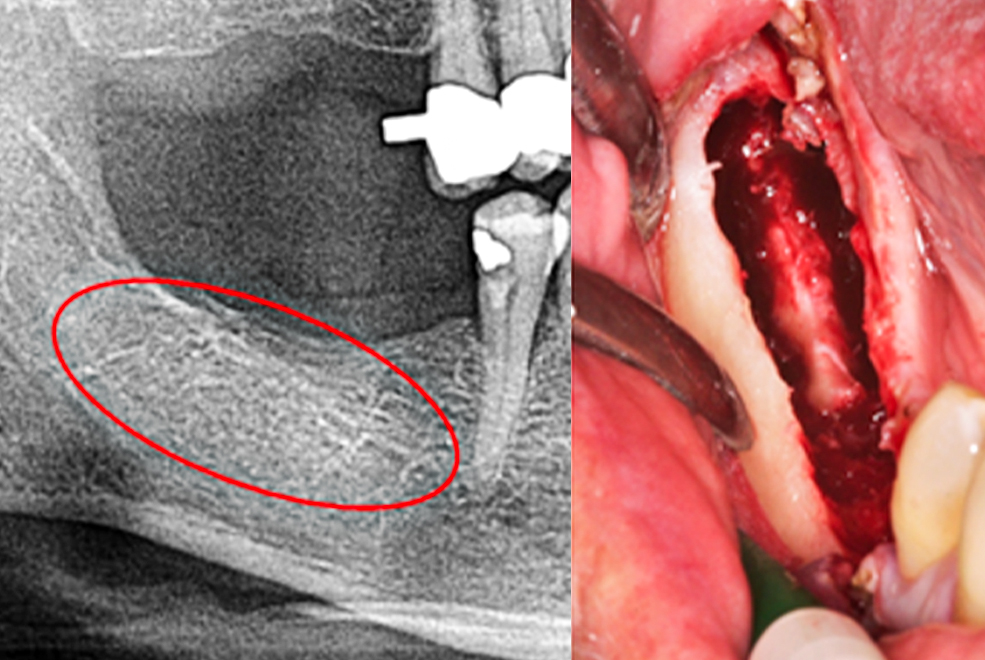

Der Glaube an unbegrenzte Aussagekraft der Röntgendiagnostik wird hinterfragt und durch die Anwendung einer trans-alveoären Ultraschallsonographie (TAU mit CaviTAU®) ergänzt.